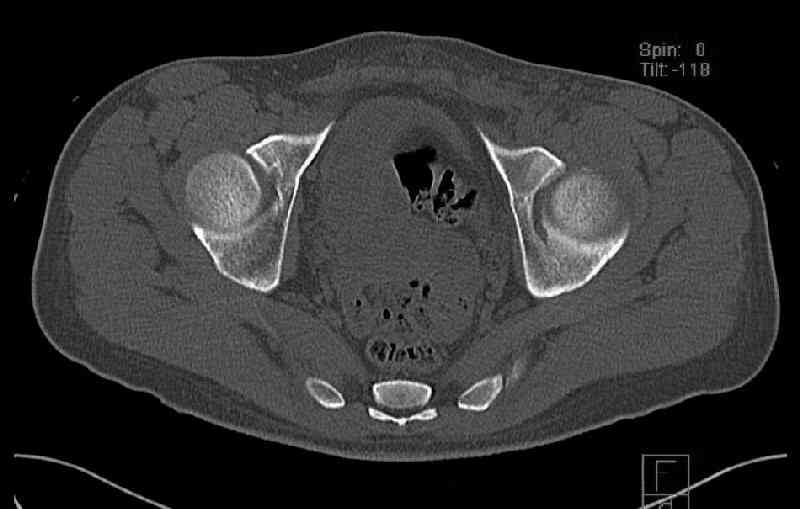

Мужчина 33 лет получил травму в шахте (придавило вагонеткой) 6 недель назад. Изолированное повреждение вертлужной впадины.

В местной больнице отлежал несколько недель на вытяжении. После выписки амбулатрный травматолог направил в институт. На сегодня, похоже, уже имеется неправиильное сращение. См. картинки.

Dear all, A male 23 y.o. injured 6 weeks ago - mine trauma, impacted by a carriage. Isolated injury of the acetabulum. At the initial hosptial was on bed traction some weeks. After discharge visited anotheк orthopaedic surgeon who referred him to our unit. To date looks like a malunion. Images attached. The question is about what to do now - either leave it as is or perform open reduction? If the latter what approach, reduction manoeuvres and fixation would you advice? Thx in advance!